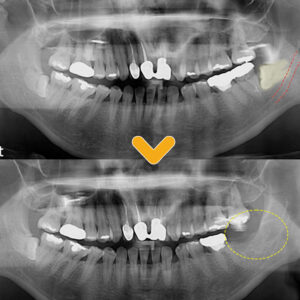

20. 수암동치과 양쪽 어금니 모두 빠진지 오래되어 식사가 불편해요.

수암동치과 양쪽 어금니 모두 빠진지 오래되어 식사가 불편해요.   안녕하세요. 모든 진료에 진심을 다하는 곳, 더플러스치과입니다. ​ 현대 평균 연령이 높아지면서 초고령화 시대가 되고 있는데요.   나이를 먹으면서 신체도 자연스럽게 노화되기 마련입니다.   치아 역시 노화로 인한 잇몸의 약화가 생겨 더보기…